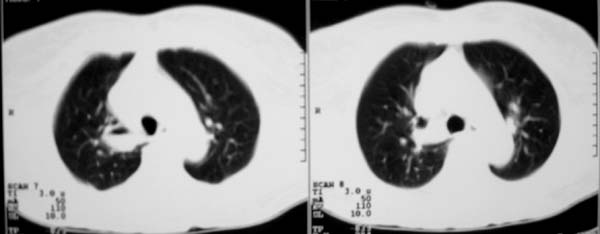

以下是引用zjzjr在2007-8-30 22:22:00的发言:[br]右上肺肺囊肿合并感染.右下肺肺大泡.左肺舌段感染.